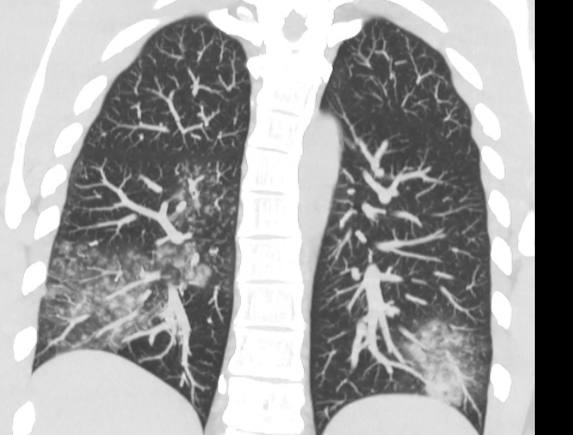

Снимок легких

Легені, уражені метапневмовірусом. Фото: Ольга Голубовська

Вона також додала, що зараження відбувається крапельним шляхом, епізоди можуть повторюватись протягом життя. Захворювання частіше є легким та супроводжується нежитем та кашлем, але може бути тяжким із розвитком прогресуючої дихальної недостатності.